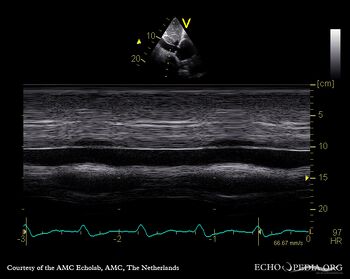

| Continuous-wave signal of tricuspid regurgitation